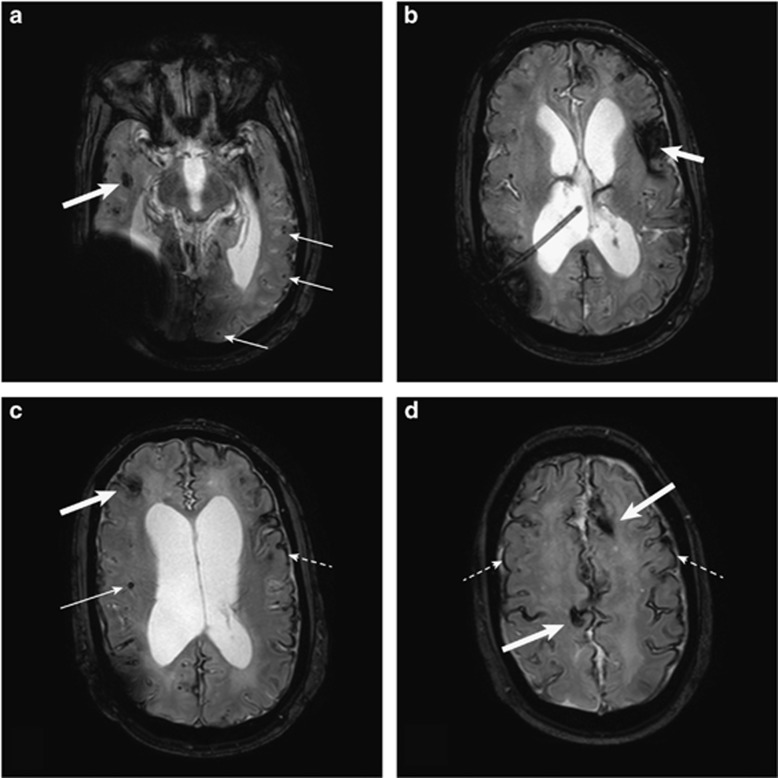

The patient carrying the c.*331_*332del variant was diagnosed with probable CAA based on multiple spontaneous lobar and subarachnoid hemorrhages with diffuse superficial siderosis, starting from the age of 39 years. His personal medical history was marked by spina bifida with ventriculoperitoneal shunting at birth, which was properly functioning since first placement and after last revision, performed at 12 years. At the age of 39, he presented spontaneous cortical parietal bilateral subarachnoid hemorrhages revealed by cephalalgia and delirium. Replacement of shunting was decided. One week later, cerebral MRI showed a right frontal hematoma, distant from the shunting trajectory. Moreover, during the following months and in the absence of any new medical event or shunt malfunction, he presented several spontaneous lobar hematomas: latest cerebral MRI showed, at the age of 41, right temporal, frontal, fronto-temporal and left frontal and frontotemporal lobar cortical hematomas, as well as numerous cortical microbleeds in all cerebral territories, diffuse superficial siderosis (Figure 1), white matter hyperintensities, and no bleeding in deep gray matter. Taking these arguments together, the diagnosis of CAA was highly probable. He had no family history of CAA. His APOE genotype was 3–4. Neither APP pathogenic variant nor APP locus duplication was detected. Sequencing of APP 3'UTR revealed a previously unreported two-base pair deletion, c.*331_*332del (r.*331_*332del). The patient was from Sub–Saharan African origin. To make sure that this variant is not frequently encountered in this ethnic group, we screened the presence of this variant in 175 controls originating from the same region of Africa. None of them carried this variant. The patient's unaffected mother did not carry the c.*331_*332del variant. The patient's father's DNA was unavailable (sudden death at the age of 70 by unknown cause). Expression analyses by RT-QMPSF revealed a ~1.5-fold increased level of the APP mRNA transcript in the patient (mean±SD: 1.47±0.06), while the analysis of his mother's RNA revealed a normal level of the APP mRNA transcript (1.12±0.06, Table 3).

Figure 1.

T2*-weighted cerebral MRI of the patient carrying the APP c.*331_*332del variant at the age of 41 years, showing cortical and subcortical microbleeds (a and c, solid arrows), lobar hematomas (a–d heavy arrows) and superficial siderosis (c and d, dotted arrows).